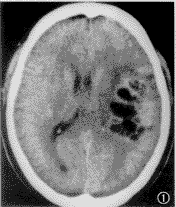

膠質母細胞瘤好發於中老年人,平掃表現為混雜密度腫塊,邊緣模糊不清,可跨越中線,瘤周水腫明顯,占位效應嚴重,增強掃描腫瘤呈花環狀強化,環壁厚薄不均,且不規則。